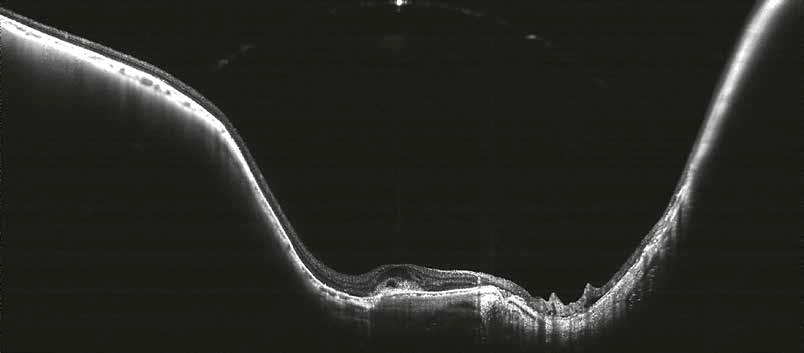

The curvature of the retina (especially posterior staphyloma) is well visualized in this Myopic Choroidal Neovascularization (mCNV) thanks to the 5.3 mm scan depth.